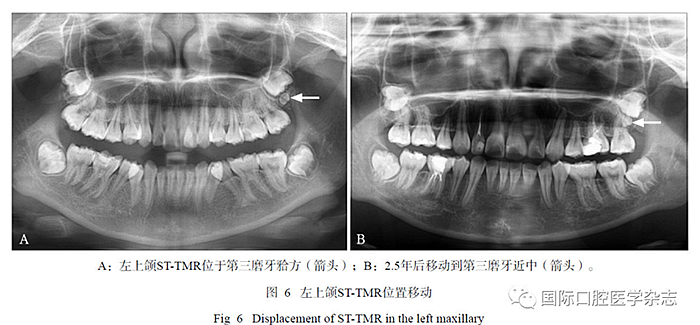

在17例有隨訪拍片的患者中,2例新增STTMR,其中1例患者第一、第二次拍片年齡分別為10歲、13歲(間隔2年7個(gè)月),另1例患者第一次、第二次拍片年齡分別為9歲、11歲(間隔2年,圖5);1例發(fā)生位置改變,ST-TMR由上頜第三磨牙方向近中移動(dòng)(間隔2.5年,圖6)。

ST-TMR在生長(zhǎng)發(fā)育中可發(fā)生位置移動(dòng),1例患者前后間隔2.5年的曲面體層片對(duì)比,發(fā)現(xiàn)左上頜ST-TMR在發(fā)育中由第三磨牙方向近中移動(dòng),這種現(xiàn)象符合恒牙生長(zhǎng)萌出過(guò)程中向近中移動(dòng)的一般規(guī)律,同時(shí)牙弓缺乏空間或擁擠也可導(dǎo)致牙胚旋轉(zhuǎn)移動(dòng),這也是造成ST-TMR或第三磨牙阻生、異位最常見(jiàn)原因之一[15]。